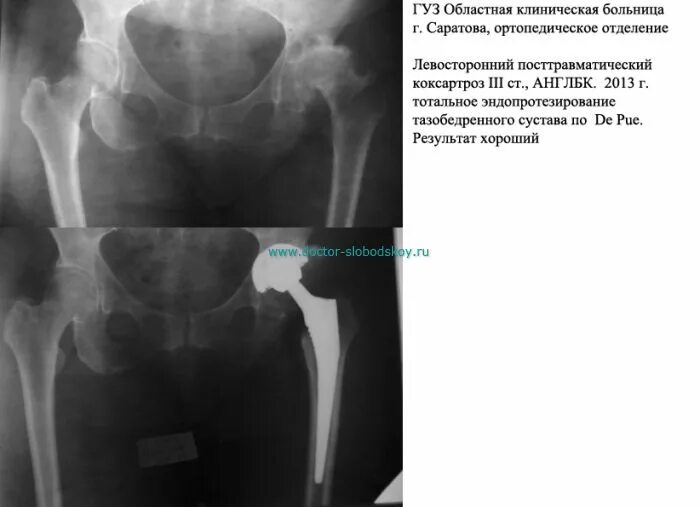

Коксартроз тазобедренного сустава код